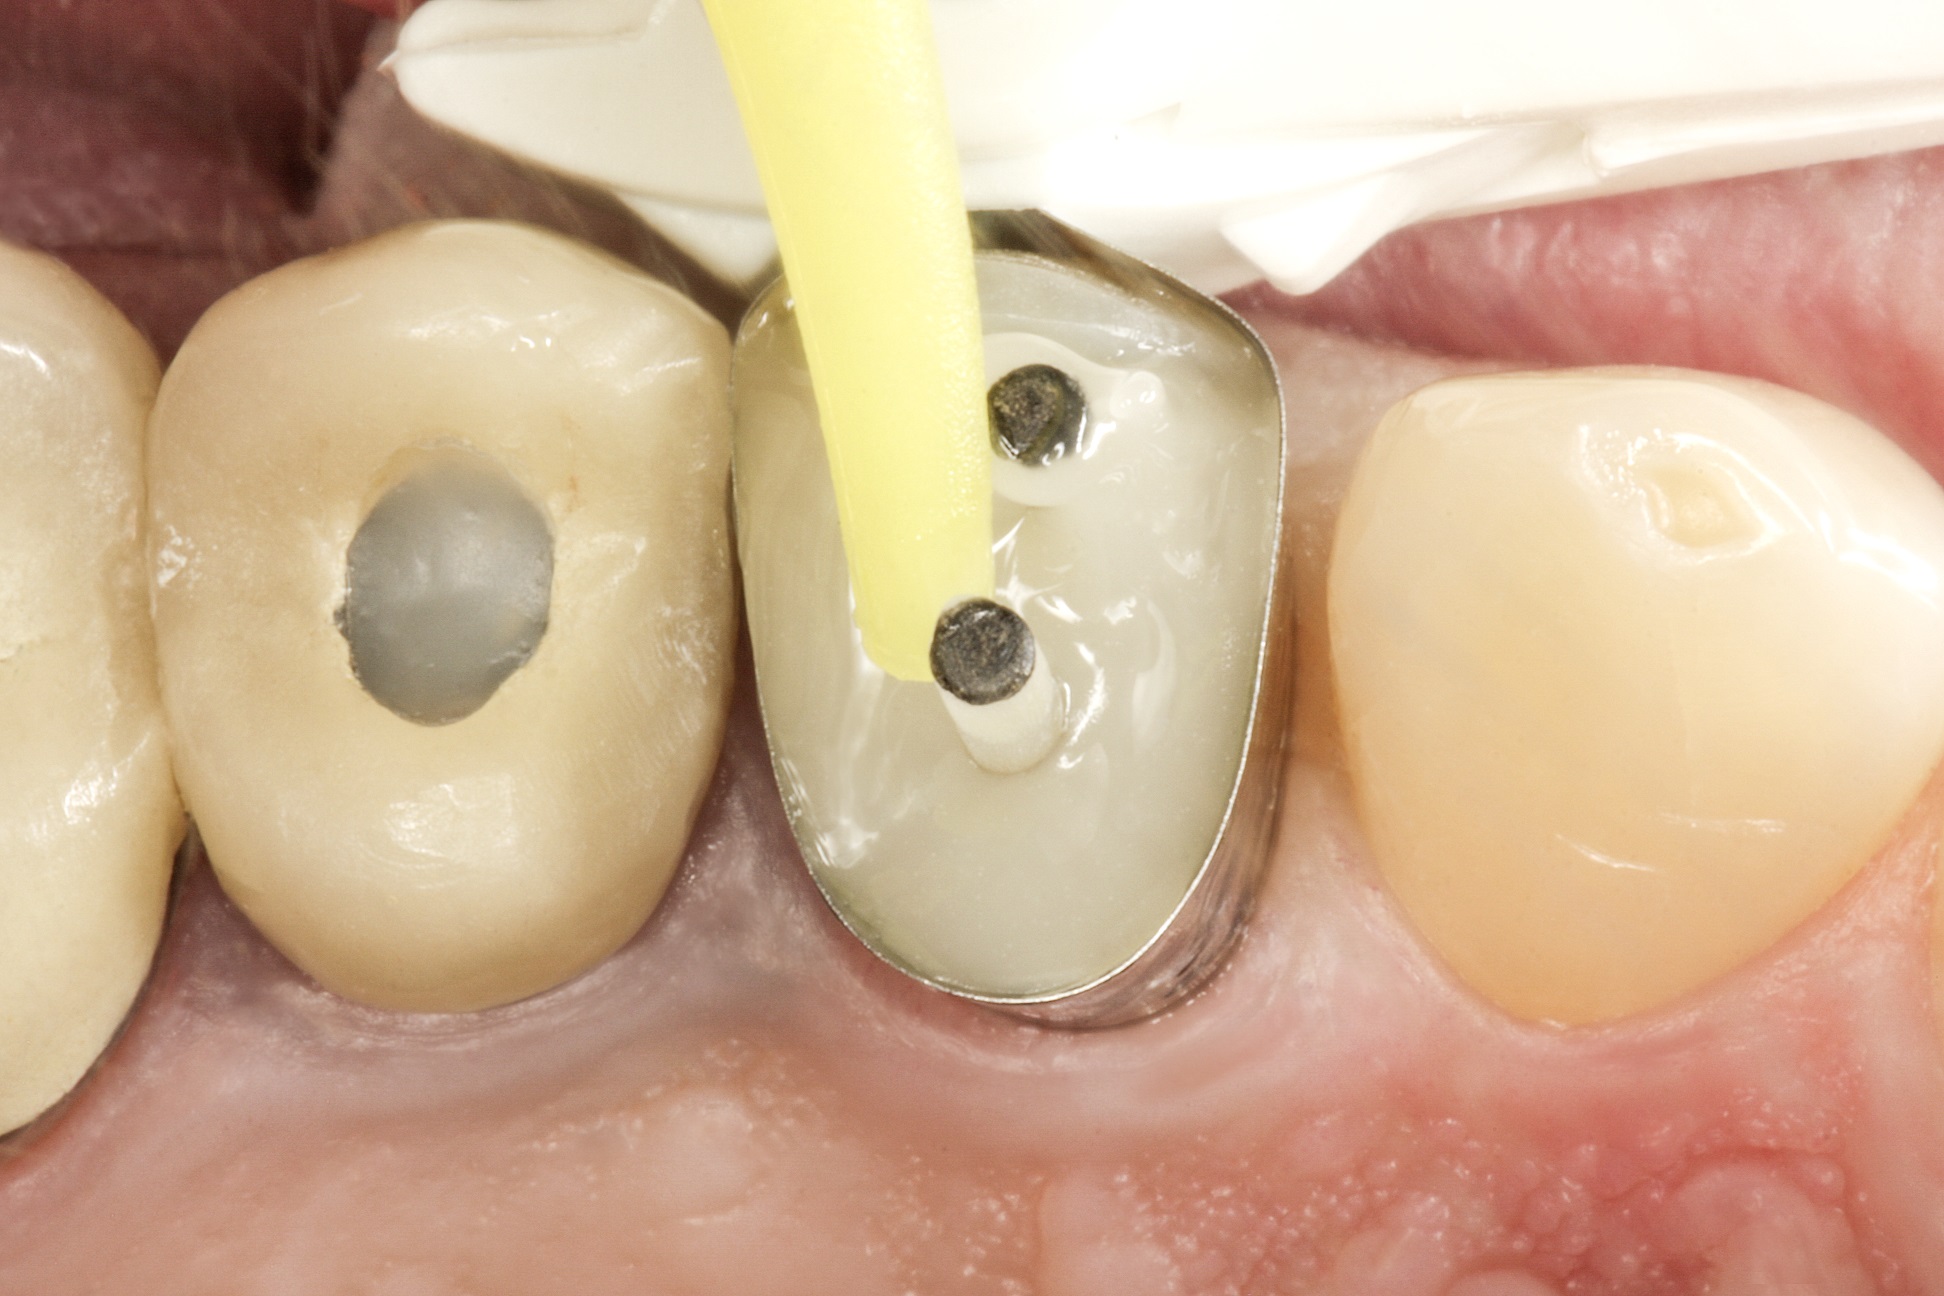

На зуб встановлюється одноразова матриця типу

Tofflemire (OmniMatrix, Ultradent). Весь підготовлений зуб протруюють

ортофосфорною кислотою протягом 20 секунд (рис. 4), а потім ретельно промивають

водно-повітряним спреєм. Після цього канали просушують паперовими штифтами.

Фото 4. Протруювання

зуба ортофосфорною кислотою.